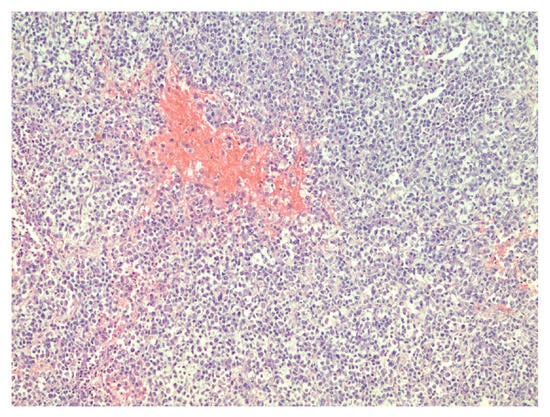

Figure 2.

Sheets of rhabdoid cells with eccentrically located nuclei and eosinophilic cytoplasm, hematoxylin–eosin, original magnification ×400.